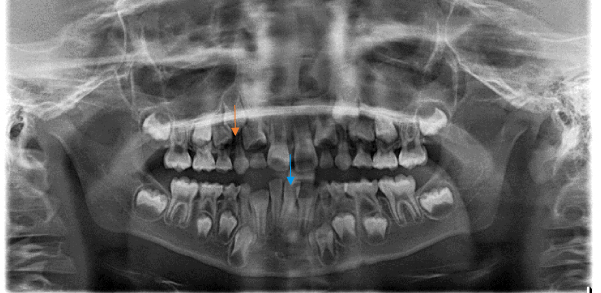

レントゲン写真

| 治療内容・期間 | 下顎の前歯が生え換わる時期に、綺麗に並ばない様子だったので、矯正をおすすめいたしました。緑の◯のところですが、ガタガタになっています。4本の前歯がガタガタだと、奥歯はもっと大きな歯が出てくるので、もっとガタガタになります。 オレンジの矢印のところは、まだ埋まっている永久歯ですが、両隣に挟まれて間隔が不足し、でられなそうな状況でした。青の矢印の歯は、根を含めて見てみるとナナメに傾いています。 2017年11月、7歳で開始しました。開始半年ほど前には、乳歯が抜けずに永久歯が生えてきたために、乳歯を抜歯しました。(2回)この時点で、顎のサイズが小さいことが予想されました。 ハイラックス上顎拡大装置を2回、下顎のリンガルアーチを5回装着し、2020年10月には拡大が完了して、あとは永久歯が出てくるのを待つ段階となりました。したがってトータルの装着期間は2年11ヶ月でした。 一度、バンドをつけている左下の歯が痛いとのことで来院されましたが、矯正で動きがあるための痛みだったので、そのまま頑張ってもらいました。また、下の装置は一度ズレて痛いというご連絡をいただいたのと、一度外れて来院されました。 また、後半ではバンドを装着していた歯が時期で抜けたとのことで、そこからは装置を外しました。 現在は定期的な虫歯のチェックと歯磨き指導に来ていただいています。 |